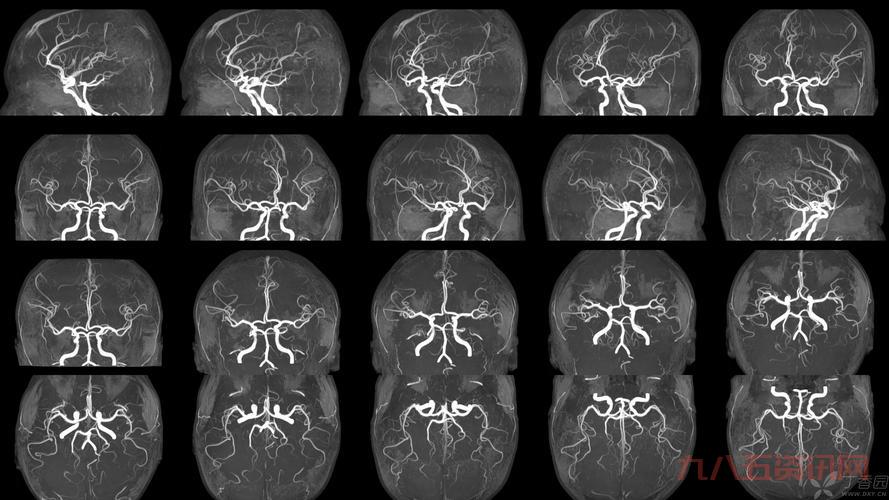

那天,我照常在家搞我的設備,突然就琢磨起這個“t2”到底是个起初我也不懂,就到處找資料,問人,可算是把“t2”是個啥弄明白。這玩意兒在醫學上還是核磁共振成像裡頭的一個關鍵指標,主要说的就是那個橫向磁化矢量恢復到一個平衡時狀態的時間,大概是這個意思。

- 像那個頸椎T2,說的就是在做核磁共振的時候,那個橫向磁化矢量衰減到最大值的百分之37所需要的時間。

- 還有那個T2信號影,就是說在核磁共振成像裡頭,組織在T2加權圖像上的表現。